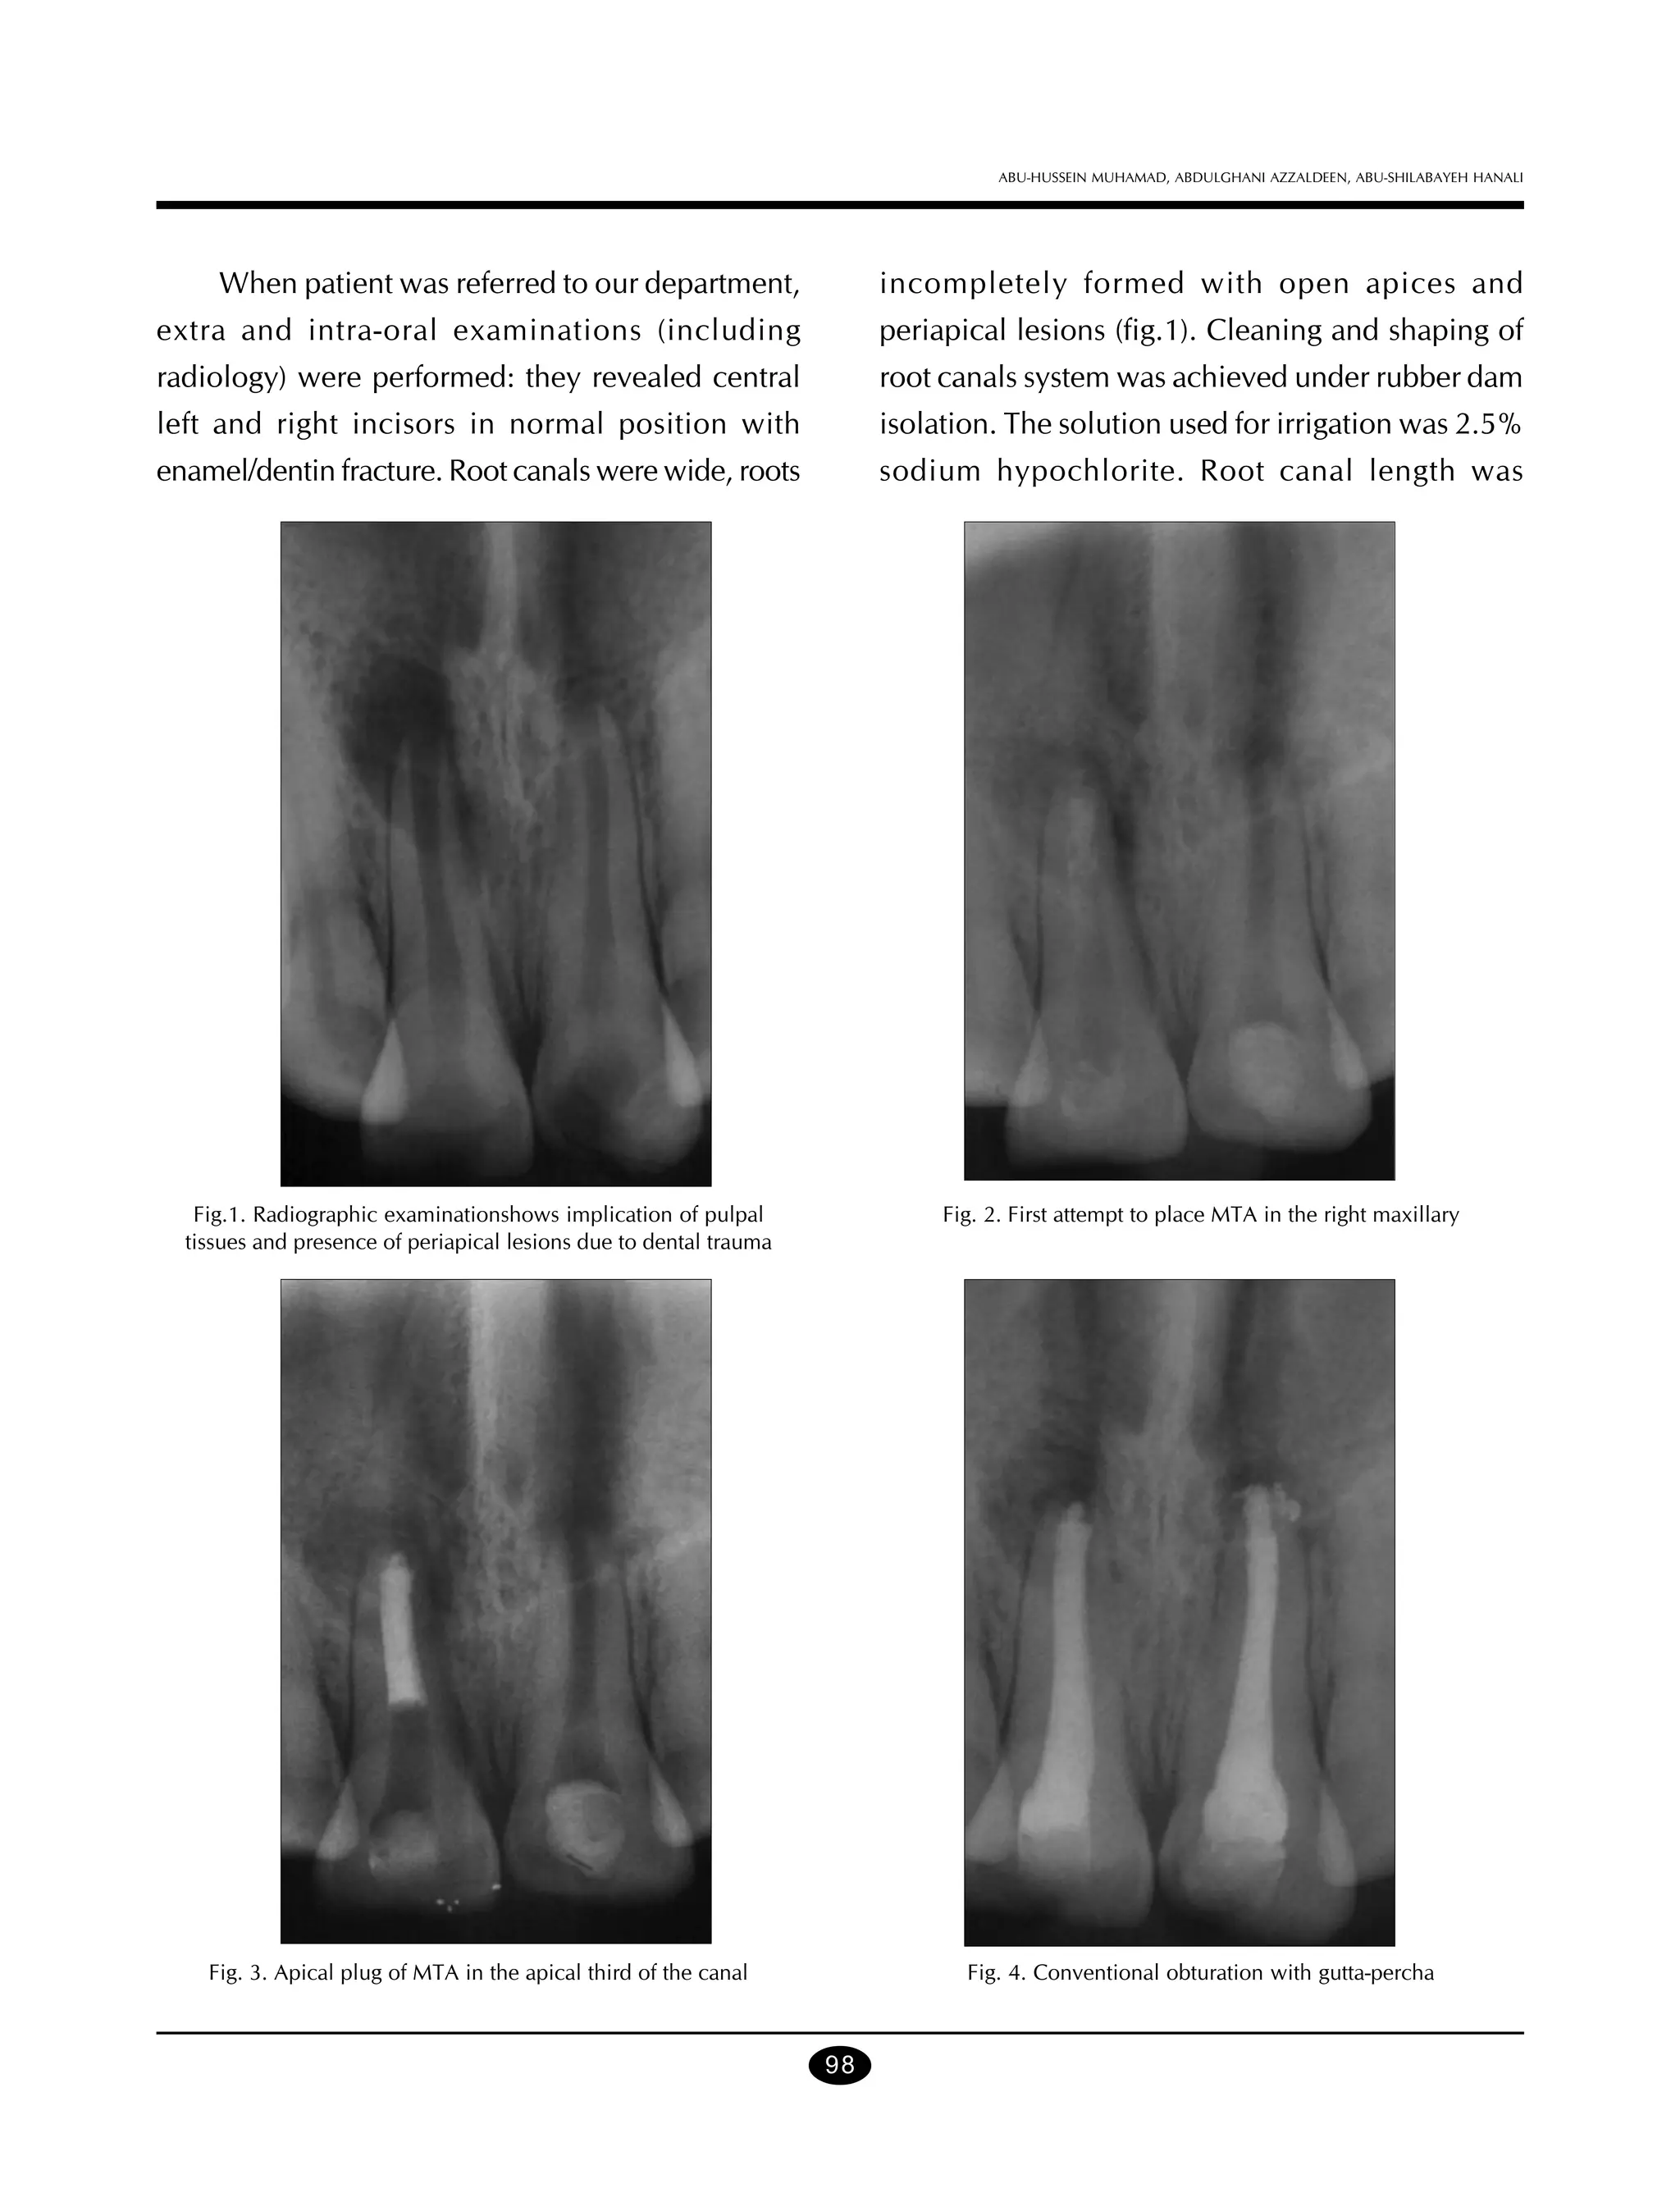

When patient was referred to our department,

incompletely formed with open apices and

extra and intra-oral examinations (including

periapical lesions (fig.1). Cleaning and shaping of

radiology) were performed: they revealed central

root canals system was achieved under rubber dam

left and right incisors in normal position with

isolation. The solution used for irrigation was 2.5%

enamel/dentin fracture. Root canals were wide, roots

sodium hypochlorite. Root canal length was

Fig.1. Radiographic examinationshows implication of pulpal

tissues and presence of periapical lesions due to dental trauma

Fig. 2. First attempt to place MTA in the right maxillary

Fig. 3. Apical plug of MTA in the apical third of the canal

Fig. 4. Conventional obturation with gutta-percha

The apical plug failed in the first attempt on the

provisional restorations and susceptibility to root

right maxillary central incisor (fig. 2), MTAR was rinsed

fractures arising from the presence of thin roots or

out with sterile water and the procedure was repeated